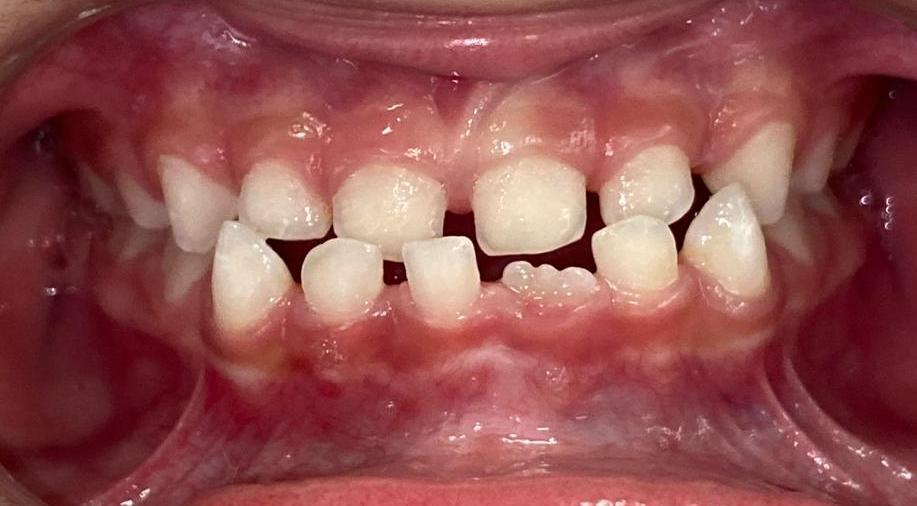

R.P.B.

ORTODONTIA MIOFUNCIONAL